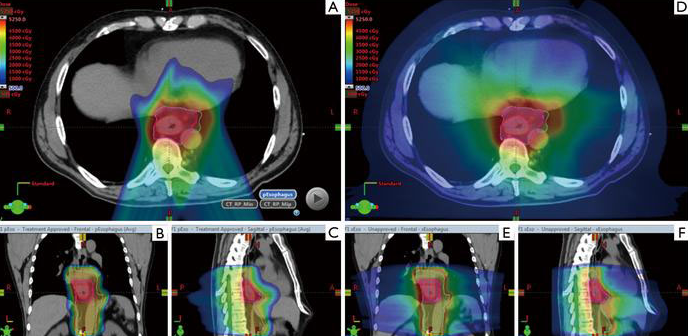

▲重离子治疗的剂量分布,图源:参考文献[3]